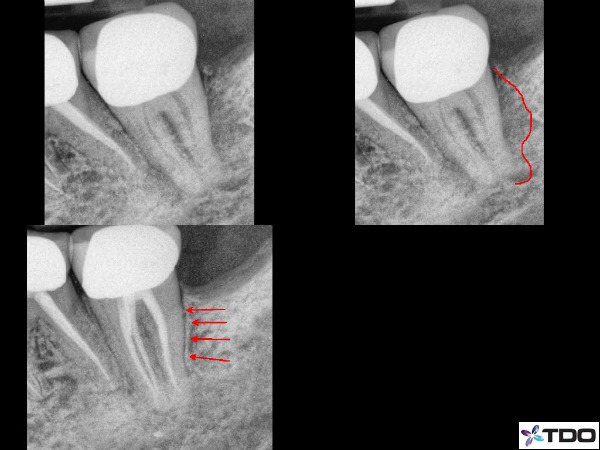

–lateral / furcal lesion caused by a primarily endodontic infection that creates the lateral and periodontal defect (figure 2,3)

Fig.2 Here is a case I treated about 1.5 years ago. The illustration shows the significant lateral and distal bone loss on the distal root of #18. The 8 month recall is on the bottom left side with red arrows showing excellent bone healing. This tooth went from a 2 mobility to rock solid before I had completed the case with 2 months of CaOH in the canals.